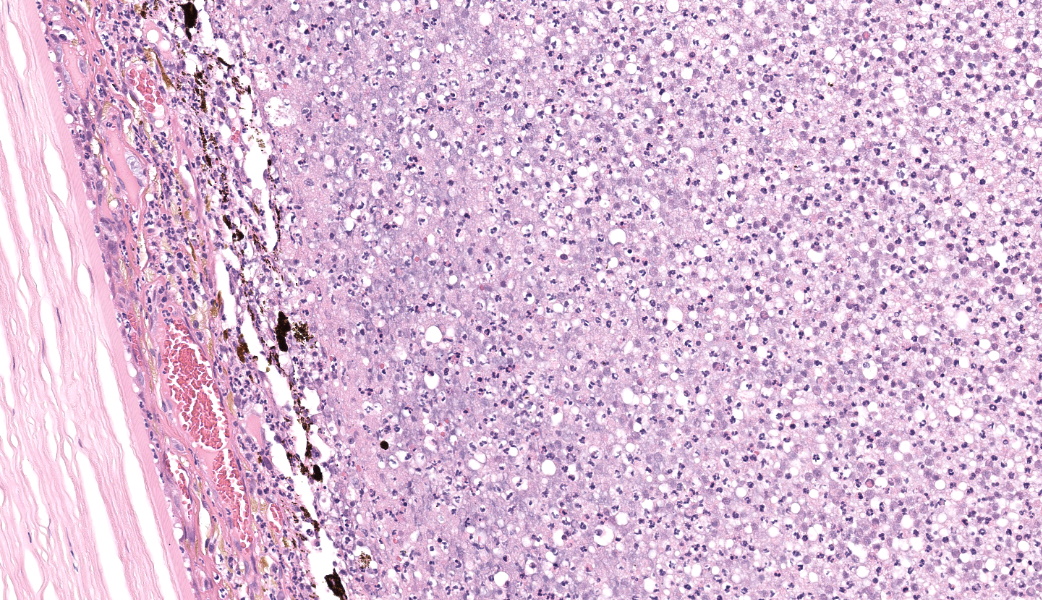

Filling all ocular chambers and coating the surfaces of intraocular structures are vast accumulations of exudate consisting of myriad degenerate and intact neutrophils, many macrophages, abundant amounts of fibrinous to proteinic material, abundant necrotic cellular debris, occasional pools of extravasated erythrocytes, and multifocal colonies of mixed bacteria (rods and coccobacilli). Centrally incorporated into the inflammatory exudates is a ruptured lens which lacks a capsule in many areas and has highly undulating free capsule margins regionally. The lenticular stroma is variably vacuolated with the following features: streaks of pallor, Morgagnian globules, many infiltrating leukocytes (mostly neutrophils), and occasional pockets of similar bacteria. The retina is diffusely detached and largely inapparent apart from remnant segments of atrophied and degenerate retina enmeshed within the exudate. Suppurative to pyogranulomatous inflammatory infiltrates multifocally extend into the iris, ciliary body, choroid, optic nerve which is significantly gliotic with rarefied neuropil, and optic nerve meninges. The iris is displaced anteriorly and multifocally abuts the posterior aspect of the cornea. The anterior chamber is severely narrow, and the drainage angle is collapsed and inapparent. The corneal stroma is moderately to markedly oedematous and contains small to moderate numbers of scattered neutrophils. The anterior corneal epithelium appears attenuated in areas. The sclera is variably thinned with multifocal often perivascular infiltrates of lymphocytes and plasma cells with variable numbers of admixed neutrophils and occasional macrophages. There are increased numbers of perilimbal pigmented cells. A thin to moderately thick layer of oedematous and inflamed granulation tissue regionally lines the mid and posterior scleral margins outside the globe and extends into a bundle of periocular skeletal muscle. In addition to infiltrates of the aforementioned inflammatory cells, the granulation tissue also contains many golden-brown pigmented macrophages (siderophages) which are concentrated at the level of the ciliary body. There is abundant haemorrhage in the retrobulbar loose connective tissue.Contributor's Morphologic Diagnoses:

Endophthalmitis, diffuse, suppurative to pyogranulomatous, severe, with lens rupture, retinal detachment and degeneration/atrophy with intraocular exudation and intralesional mixed bacteria, drainage angle collapse, keratitis, corneal oedema, scleritis and regional periscleral fibrosisContributor's Comment:

Talk about a descriptive case that made, for obvious reasons, an excellent sales pitch on why pathology is the best profession! This case provides an excellent opportunity for participants to push themselves on their ocular descriptive abilities. Many thanks to this contributor for a fantastic case! Much like the previous eye case in this conference, there was substantial discussion on ocular pathology. The most informative nuggets from that conversation included utilizing the lens capsule, which is an easily identifiable structure in the eye, to assist with orientation in a busy ocular slide such as this one. The pigmented irideal stroma, as well as the “golden” fibers of the iris, can also be used to help identify structures that might otherwise be difficult to ascertain due to the degree of damage and/or inflammation.This case had beautiful examples of iris bombe (iris pushed forward into the anterior chamber and adhered to the back of the cornea), numerous types of fibrovascular membranes (retrocorneal, preiridial, cyclitic, etc.), and a fantastic phakoclastic panuveitis from lens rupture. The six types of uveitis and their definitions were discussed and included: 1) anterior uveitis (inflammation of the iris and ciliary body), 2) posterior uveitis (inflammation of the ciliary body and choroid), 3) panuveitis (iris, ciliary body, and choroid affected), 4) chorioretinitis (inflammation of the choroid and retina), 5) endophthalmitis (inflammation of uvea, retina, and ocular cavities), and 6) panophthalmitis (all ocular structures are affected, including sclera). Being able to recognize and accurately use these terms as pathologists can provide crucial information to ophthalmologists when it comes to treating these patients.